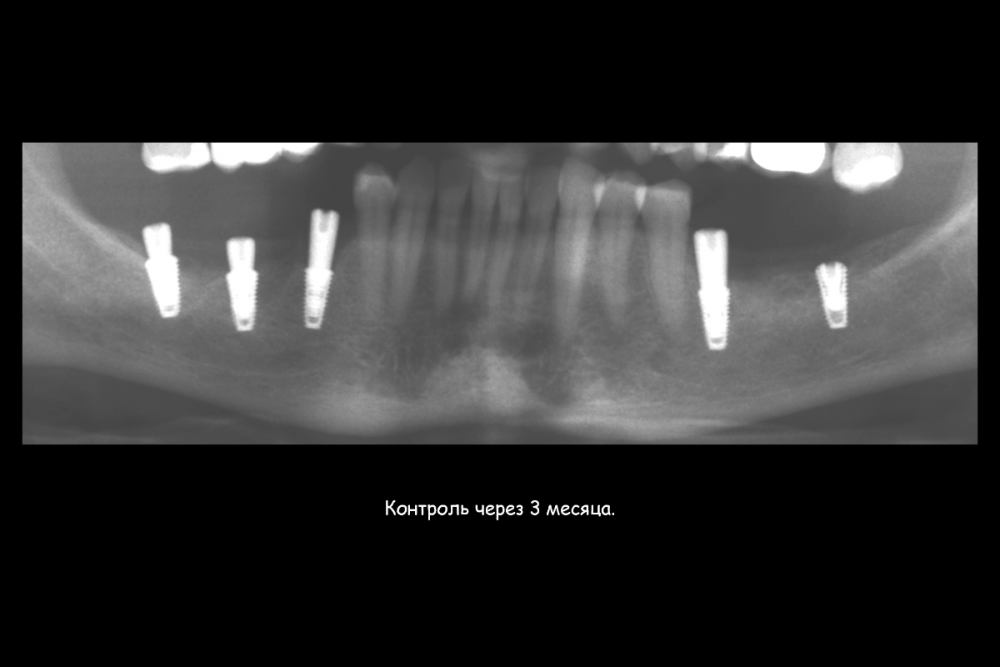

Карен Аванесов Опубликовано 23 июля, 2021 Поделиться Опубликовано 23 июля, 2021 (изменено) Этот пациент особо радует гигиеной на осмотрах, всегда очень чисто, приятно это. Важно когда пациент ответственный. По кейсу все на сгустке крови, без "проленового" рта. Изменено 23 июля, 2021 пользователем Карен Аванесов 6 3 1 Ссылка на комментарий